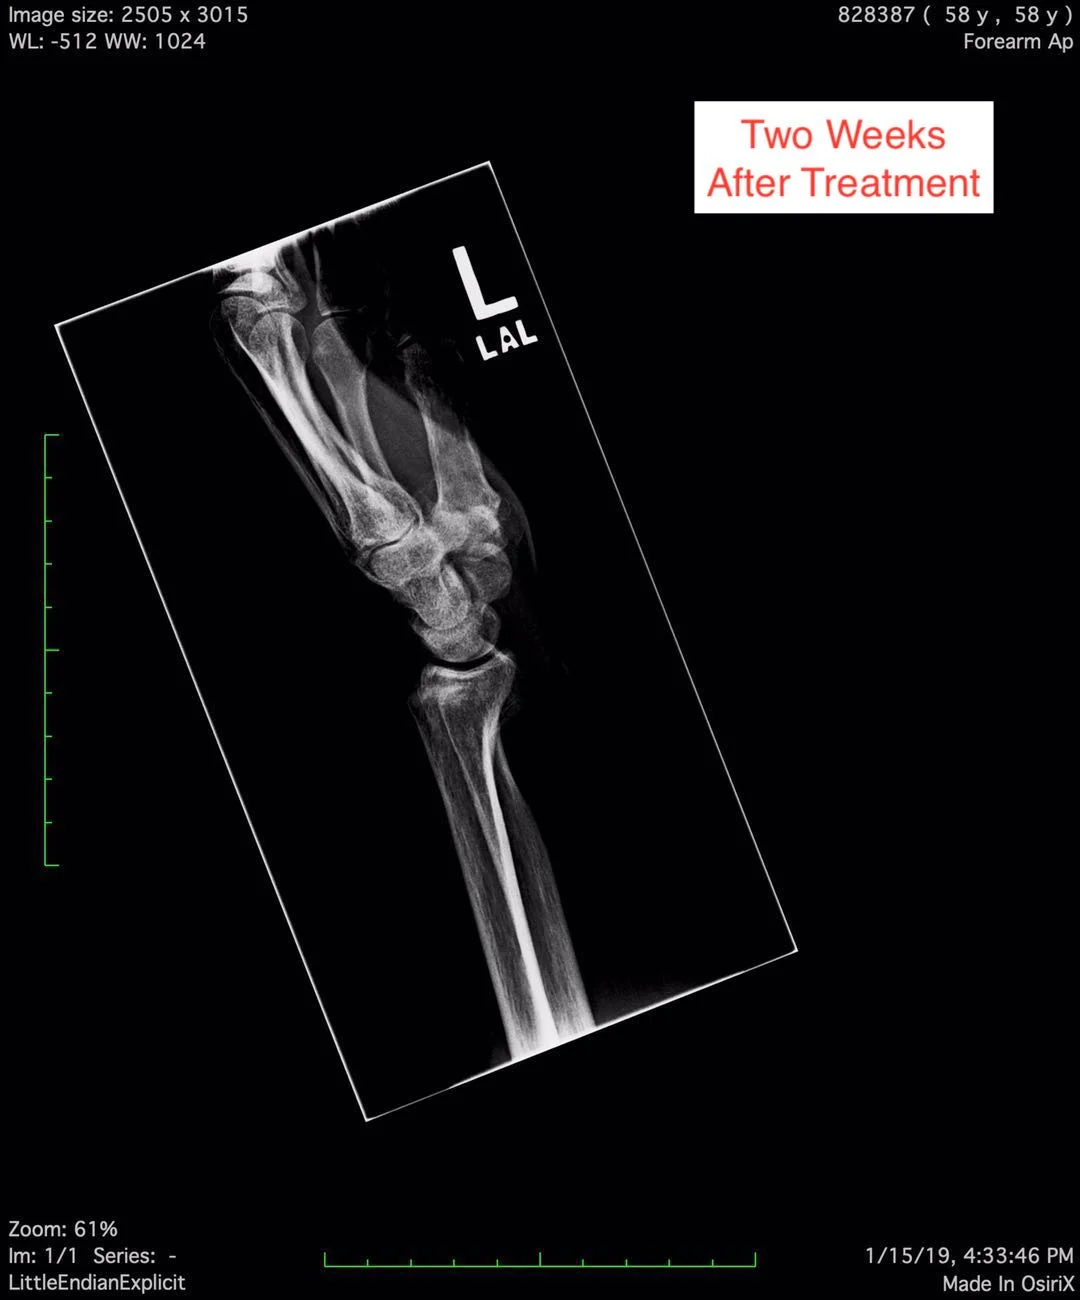

The fracture is Anti Coriolis fracture of the radial bone in the patient’s fore arm.

On this page, you can see the two X-ray pictures from before the treatment, showing the Anti Coriolis fracture of the radial bone. You can also see the X-ray pictures two weeks after the treatment, showing good bone alignment, and normal epiphyseal growth, indicating the clinical healing standard is reached.